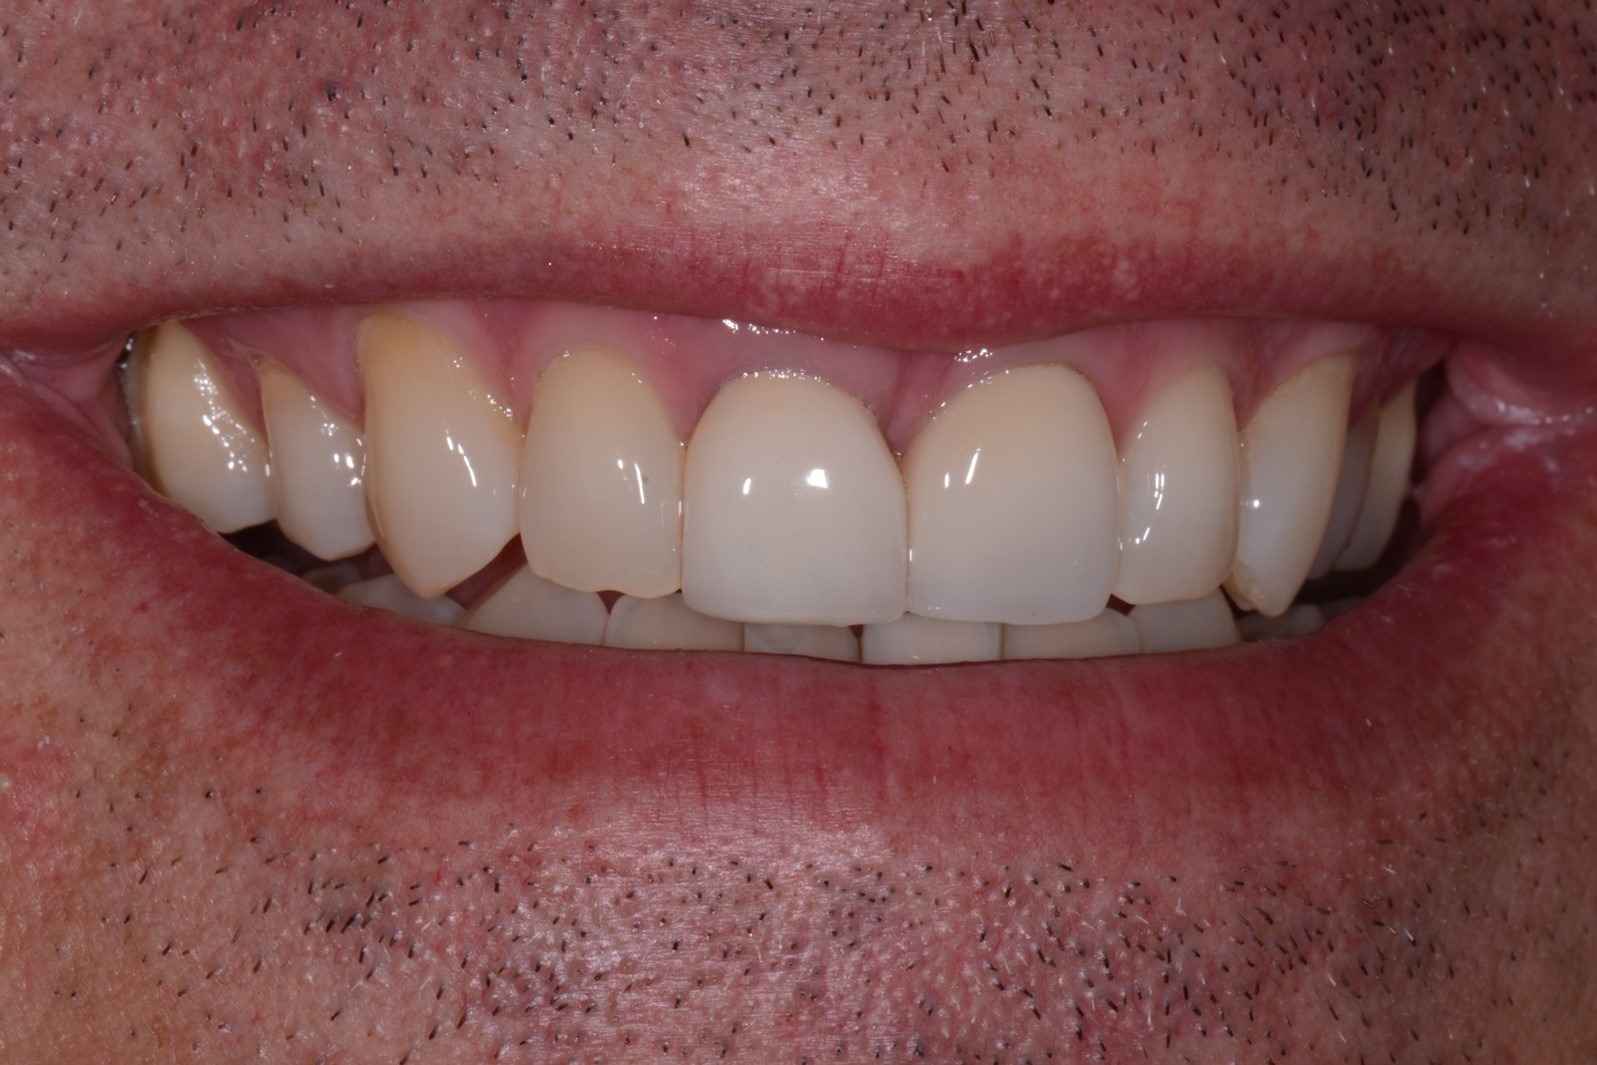

Fig 12. At 8 years post-treatment, the results of the minimally invasive approach remain an ideal esthetic implant placement, without visible damage or scar tissue from the flapless approach or connective tissue graft to thicken the biotype.

Figure 12